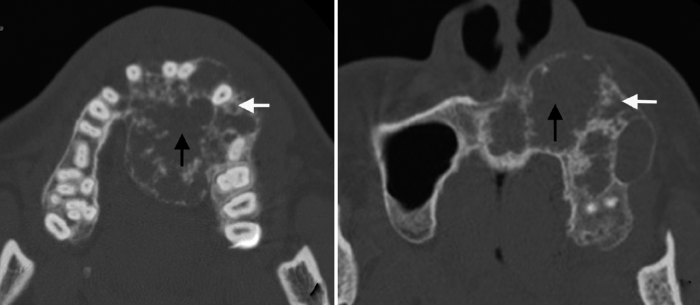

图3

促结缔组织增生型成釉细胞瘤蜂窝/皂泡型(Ⅱ型)

Figure 3

The honeycomb/soap bubble type of DA (type Ⅱ)

Axial CT images shows the scattered inhomogeneous ossifications appearing as honeycomb (white arrows) or soap bubbles (black arrows).